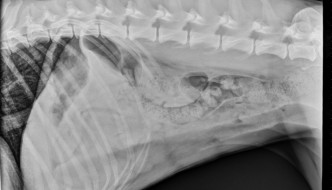

10 year old Corgi

Today's case is a 10 year old female neutered Corgi with several days of vomiting and anorexia. What is the most important finding? … [Read more...]